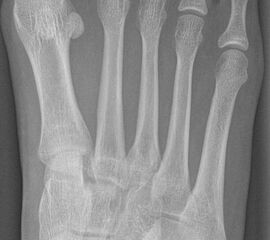

DMMO/DMDO (Distale Minimalinvasive Metatarsale Osteotomie/Distale Minimalinvasive Diaphysäre Osteotomie)

Die Indikation für eine DMMO oder DMDO (Distale Minimalinvasive Metatarsale Osteotomie/Distale Minimalinvasive Diaphysäre Osteotomie) beim Kind mit wachsendem Skelett ist nicht die klassische Metatarsalgie des Erwachsenen. In der Kinderorthopädie kann eine gute Indikation für die DMMO oder für eine DMDO der Ballen-Hohl-Fuß mit Metatarsalgie sein. Wird z. B. bei einer frühen Hohlfußkorrektur das Metatarsale I für eine bessere Rückfußeinstellung extendiert und zur Aufhebung der Extensorensubstitution die Sehne des M. tibialis posterior transferiert, kann sich im Verlauf eine Dysbalance der Metatarsalia entwickeln und eine Metatarsalgie unter II-IV auftreten. Mit einer DMDO werden die Köpfchen II-IV effektiv angehoben und die Beschwerden gebessert (Abb. 17 und 18).

Abb. 18 a-b: Beispiel einer DMDO beim Hohlfuß d.p. (dorso-plantare) Ansicht (a) und schräge Ansicht (b).